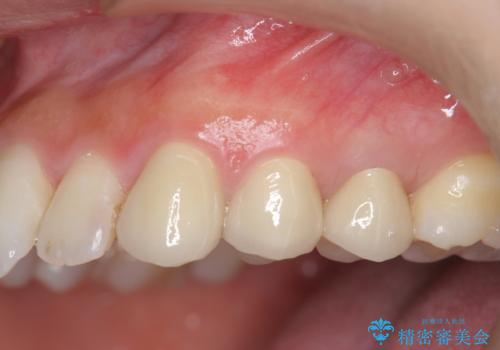

- 歯ぐきの腫れや、歯の内部が黒く見えることからの虫歯の治療を求めて来院されました。

虫歯が大きかったことから、神経の温存はできたものの歯ぐきよりも深い虫歯の問題を解決するため、部分矯正治療を併用したセラミック治療を行うこととしました。

当初、歯ぐきよりも深い虫歯の存在や、歯のポジションに問題がありましたがマルチブラケットを用いた部分矯正で行うことで歯の挺出同時に適切な位置へと歯を移動させ、歯周環境を整えたセラミック治療を行うことができました。